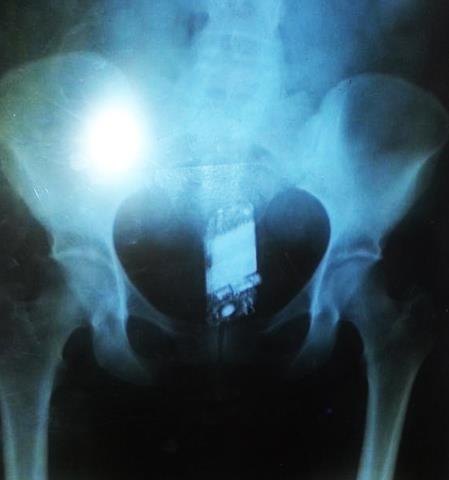

Ela foi levada para fazer exame de raio-X no Hospital João Paulo II, e verificou-se que ela escondia as serras.

Apenado foi flagrado com os objetos ilícitos ao passar por um detector de metal

A acusada, identificada pelas iniciais do nome N.B.S de 27 anos foi flagrada com quatro serrinhas de aço, que seriam entregues a apenados.

De acordo com informações obtidas pela reportagem do Extra de Rondônia, F. S. S., de 22 anos, foi detida por Agentes Penitenciários quando se preparava para visitar o marido identificado como Leandro G.S., vulgo “Serafim”.